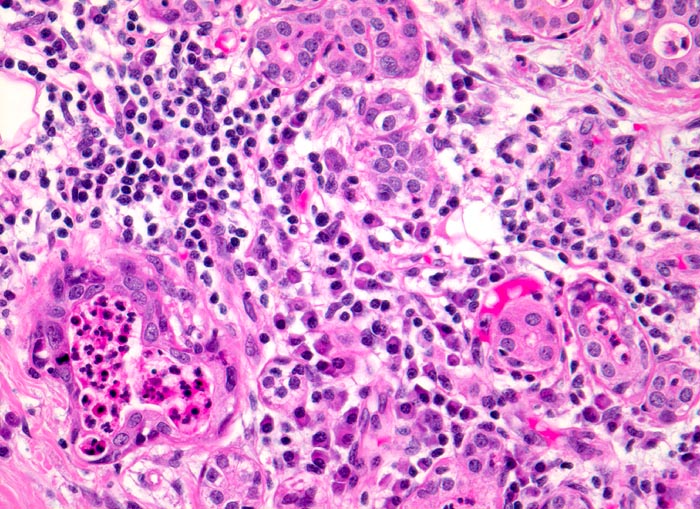

PathoPic – image database / PathoPic ID 3320 - floride chronische Sialadenitis bei Sialolithiasis.

floride chronische Sialadenitis bei Sialolithiasis.

Glandula submandibularis

Drüsenläppchen mit ödematösem lymphoplasmazellulär infiltriertem Stroma. Zwei Drüsenlumina sind leicht erweitert und enthalten Eiter. Die Drüsenazini sind atrophiert.

Histologie

200